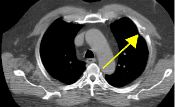

Patient below has a history of prostate cancer and melanoma with known metastasis to T7.   PET scan was performed to rule out radiation changes versus recurrence at T7.   The PET scan was negative in T7 (thus compatible with radiation changes) but serendipitously revealed marked uptake in the left upper hemithorax (Fig. 1-2 coronal and axial PET tomograms).   A subsequent CT with coronal reformation demonstrated a destructive rib lesion consistent with metastasis (Fig. 3-4).   This changed patient management who subsequently underwent chemotherapy.

Figure 1Figure 2Figure 3Figure 4